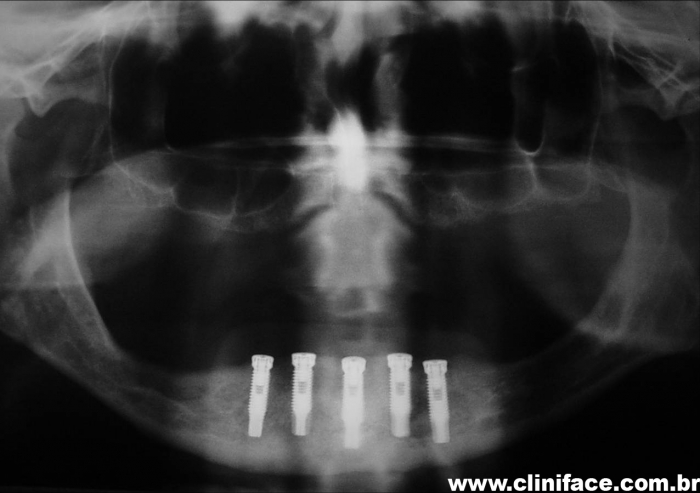

Raio X com implantes instalados

Raio X com prótese fixa instalada